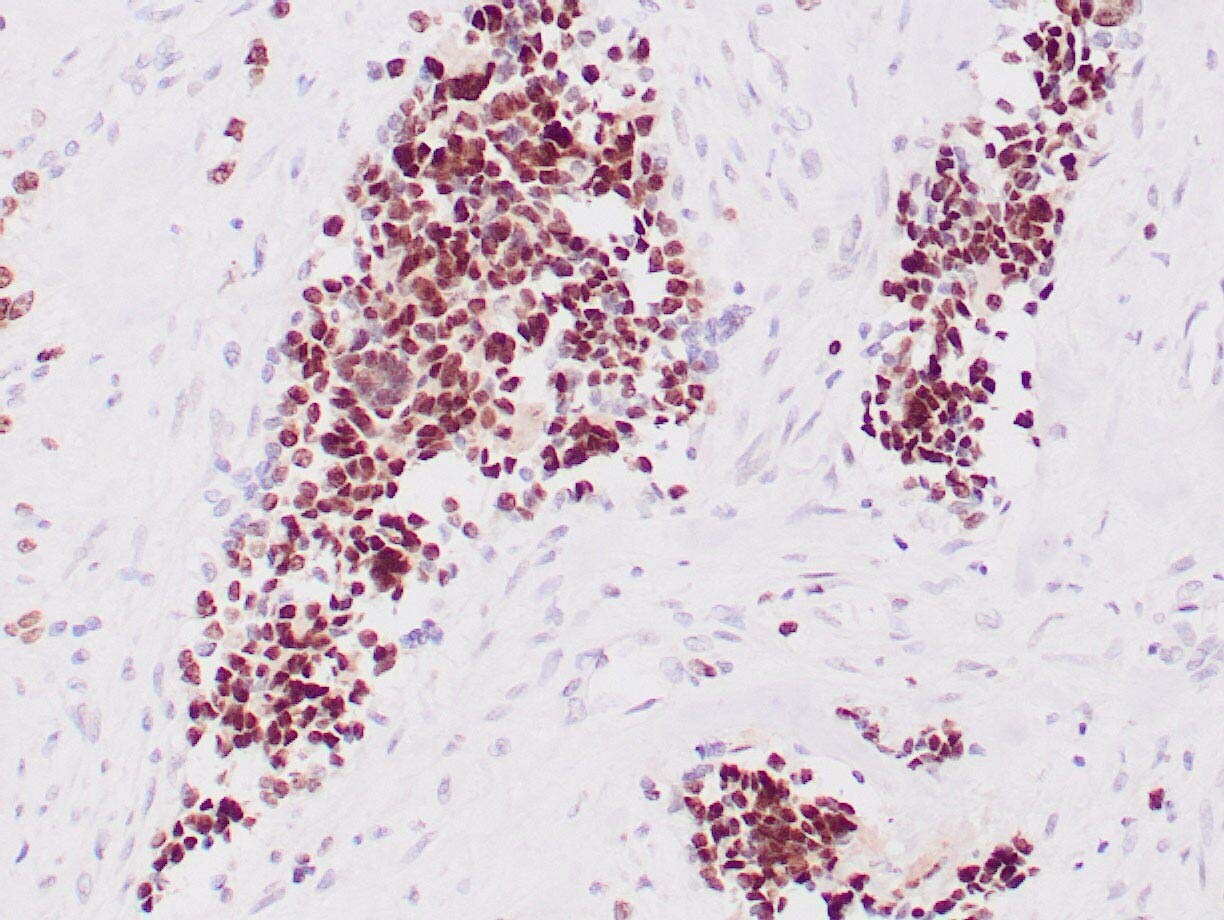

- Main image

- Experimental details

- Human rhabdomyosarcoma stained with anti-Myogenin antibody using peroxidase-conjugate and DAB chromogen. Note nuclear staining of tumor cells.